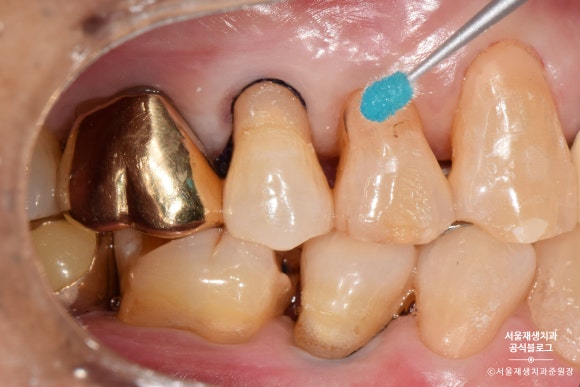

전방치아는 레진으로, 후방치아는 GI로 치료한 사례

여러 치아에 동시에 발생한 치경부마모증을 치료한 사례입니다.

환자분과 거울을 보며 상의한 결과,

잘 보이는 전방 치아는 레진으로,

잘 보이지 않는 후방 치아는 글라스아이오노머로 치료하기로 결정했습니다.

치아의 목 부분, 다시 말해 잇몸과의 경계 부위에

짙은 오렌지색의 띠가 보이시나요?

치아의 겉면은 하얗고 투명한 법랑질인데 반해,

치아의 속살은 노랗고 불투명한 상아질입니다.

법랑질이 모두 마모되어 상아질이 노출되었고,

법랑질에 비해 무른 상아질이 안으로 파고들듯이 마모되고 있는 상태였습니다.

제법 진행이 많이 된 치아를 선별하여

총 4개의 치아를 치료하기로 했습니다.

노란색으로 표시된 치아들은 상대적으로 전방에 위치하여 레진으로 치료하기로 했습니다.

연두색으로 표시된 치아들은 상대적으로 후방에 위치하여, 심미성이 조금 떨어지더라도 비용이 저렴한 글라스아이오노머로 치료하기로 했습니다.

레진이 접착될 부위를 깨끗하게 소독하고

약제를 도포합니다.

레진을 치아에 접착시키는 약제를 도포합니다.